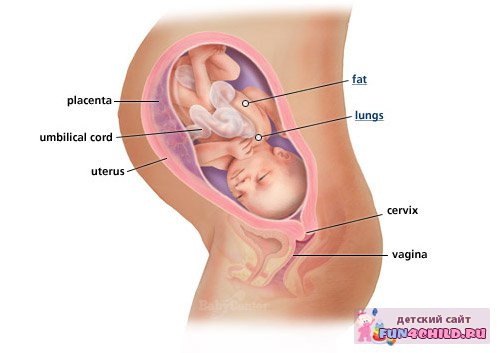

на терміні вагітність 33 - 34 тижні малюк займає майже все вільне місце, тому він займає остаточне положення в матці. Зазвичай в цій позі він і з'являється на світ, хоча бувають рідкісні випадки, коли малюк при невеликій масі може перевернутися і на останніх тижнях вагітності. Слух і зір удосконалюються, тепер він не тільки розрізняє голоси, але і інтонації, про що повинні пам'ятати мама і навколишні її люди.

Дитина вже сформований. Підшкірний жир продовжує накопичуватися. Шкіра стає все блідіше і поступово розгладжується. Уже округлилися щічки, а особа набула милі риси новонародженої дитини. Очі закриті, але райдужна оболонка продовжує формувати колір, закладений на генетичному рівні. Органи вже практично сформовані і готові до своєї діяльності. На цьому тижні інтенсивно розвиваються наднирники.

В утробі дитина «дозріває», у нього є і працюють всі органи. Незабаром він опуститься в область тазу, і мамі буде легше дихати.

На терміні 35 тижнів вагітності дитина остаточно вибирає для себе зручне положення, в якому він залишиться до появи на світ.

Найчастіше, на такому терміні багато діток правильно лягають: вниз голівкою, личком до спини мами. Подібну позицію називають головним передлежанням. Ще не зрослися кістки черепа, тому можлива їх легка деформація при проходженні через родові шляхи, ніж трохи полегшується родовий процес. Для малятка зручно і комфортно розташовуватися головкою вниз, також в цей час природно скручування калачиком.

Животик так збільшується, що завдає чимало клопоту. Матка стає величезною, тисне на шлунок, розплющує легкі, навалюючись на діафрагму. Потрібно трішки потерпіти: в кінці 35 тижня вагітності малюк і живіт буде опускатися і жінка зможе нормально дихати.

Від пупка дно матки знаходиться на 15 см, від лобкового симфізу - на 35 см. Пупок досить витріщивши. Однак на подібному терміні для вагітності це цілком нормально. На 35 тижні вагітності малюк активно вживаємо кальцій з маминого організму. Слід додати в свій раціон молочну продукцію і незбиране молоко.